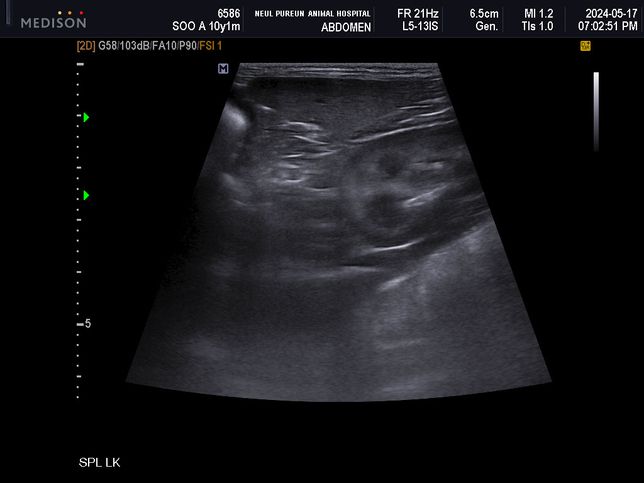

- 반려동물 건강반려동물Q. 강아지 초음파 사진 한 번 봐주실 수 있나요저희 강아지 5월에 찍었던 초음파인데 이게 비장 맞나요? 이번에 찍은 초음파에선 비장에 작은 결절이 하나 보였는데 이때도 보였던 건지 알 수 있을까요? 그 외 특이사항이 있는지도 알고 싶어요